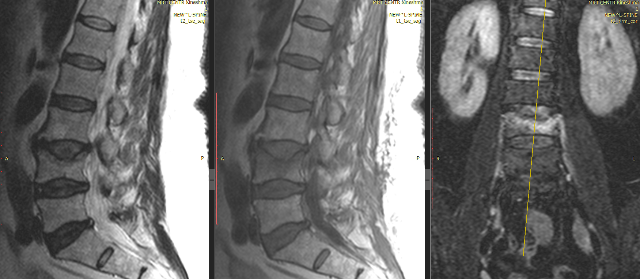

Стабильный перелом позвонка